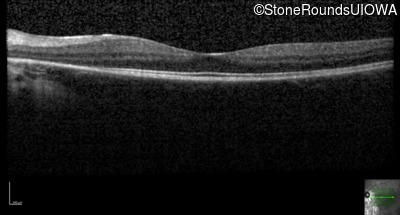

Age at visit: 14 years

This fourteen year old female has had poor vision in dim light since at least age 6.

Age at visit: 18 years

Age at visit: 18 years (Visit 2)

Age at visit: 19 years

Age at visit: 20 years

Age at visit: 22 years